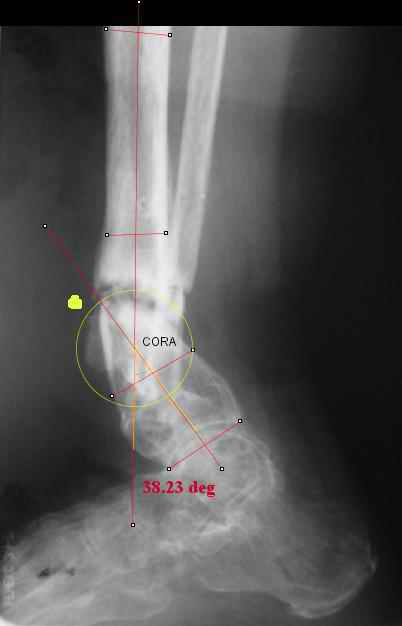

TDVC> I played with your image using some orthopedic software

TDVC> we have been developing for digital image analysis.

TDVC> a correction around the CORA through the old # will restore

TDVC> alignment without much translation.

Maybe my "embedded software" is obsolete but it hints me to place hinges at the yellow point - this must result with alignment and some lengthening without translation. What do you think?

Re the CORA.:

I think that if you locate the hinge at that site and then you rotate the foot about this point with out distraction you will be perfectly lined up. If you distract in the axis of the proximal tibia then rotate, it should still work (the hinge should still be located in the mid tibial axis). But, if you distract out of that axis then you will get translation. Does that make sense?

I looked at your image. I presume your yellow marker is the hinge axis? I think this should be at the CORA.